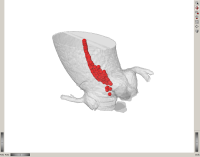

Cluster of candidate points in the ascending aorta.